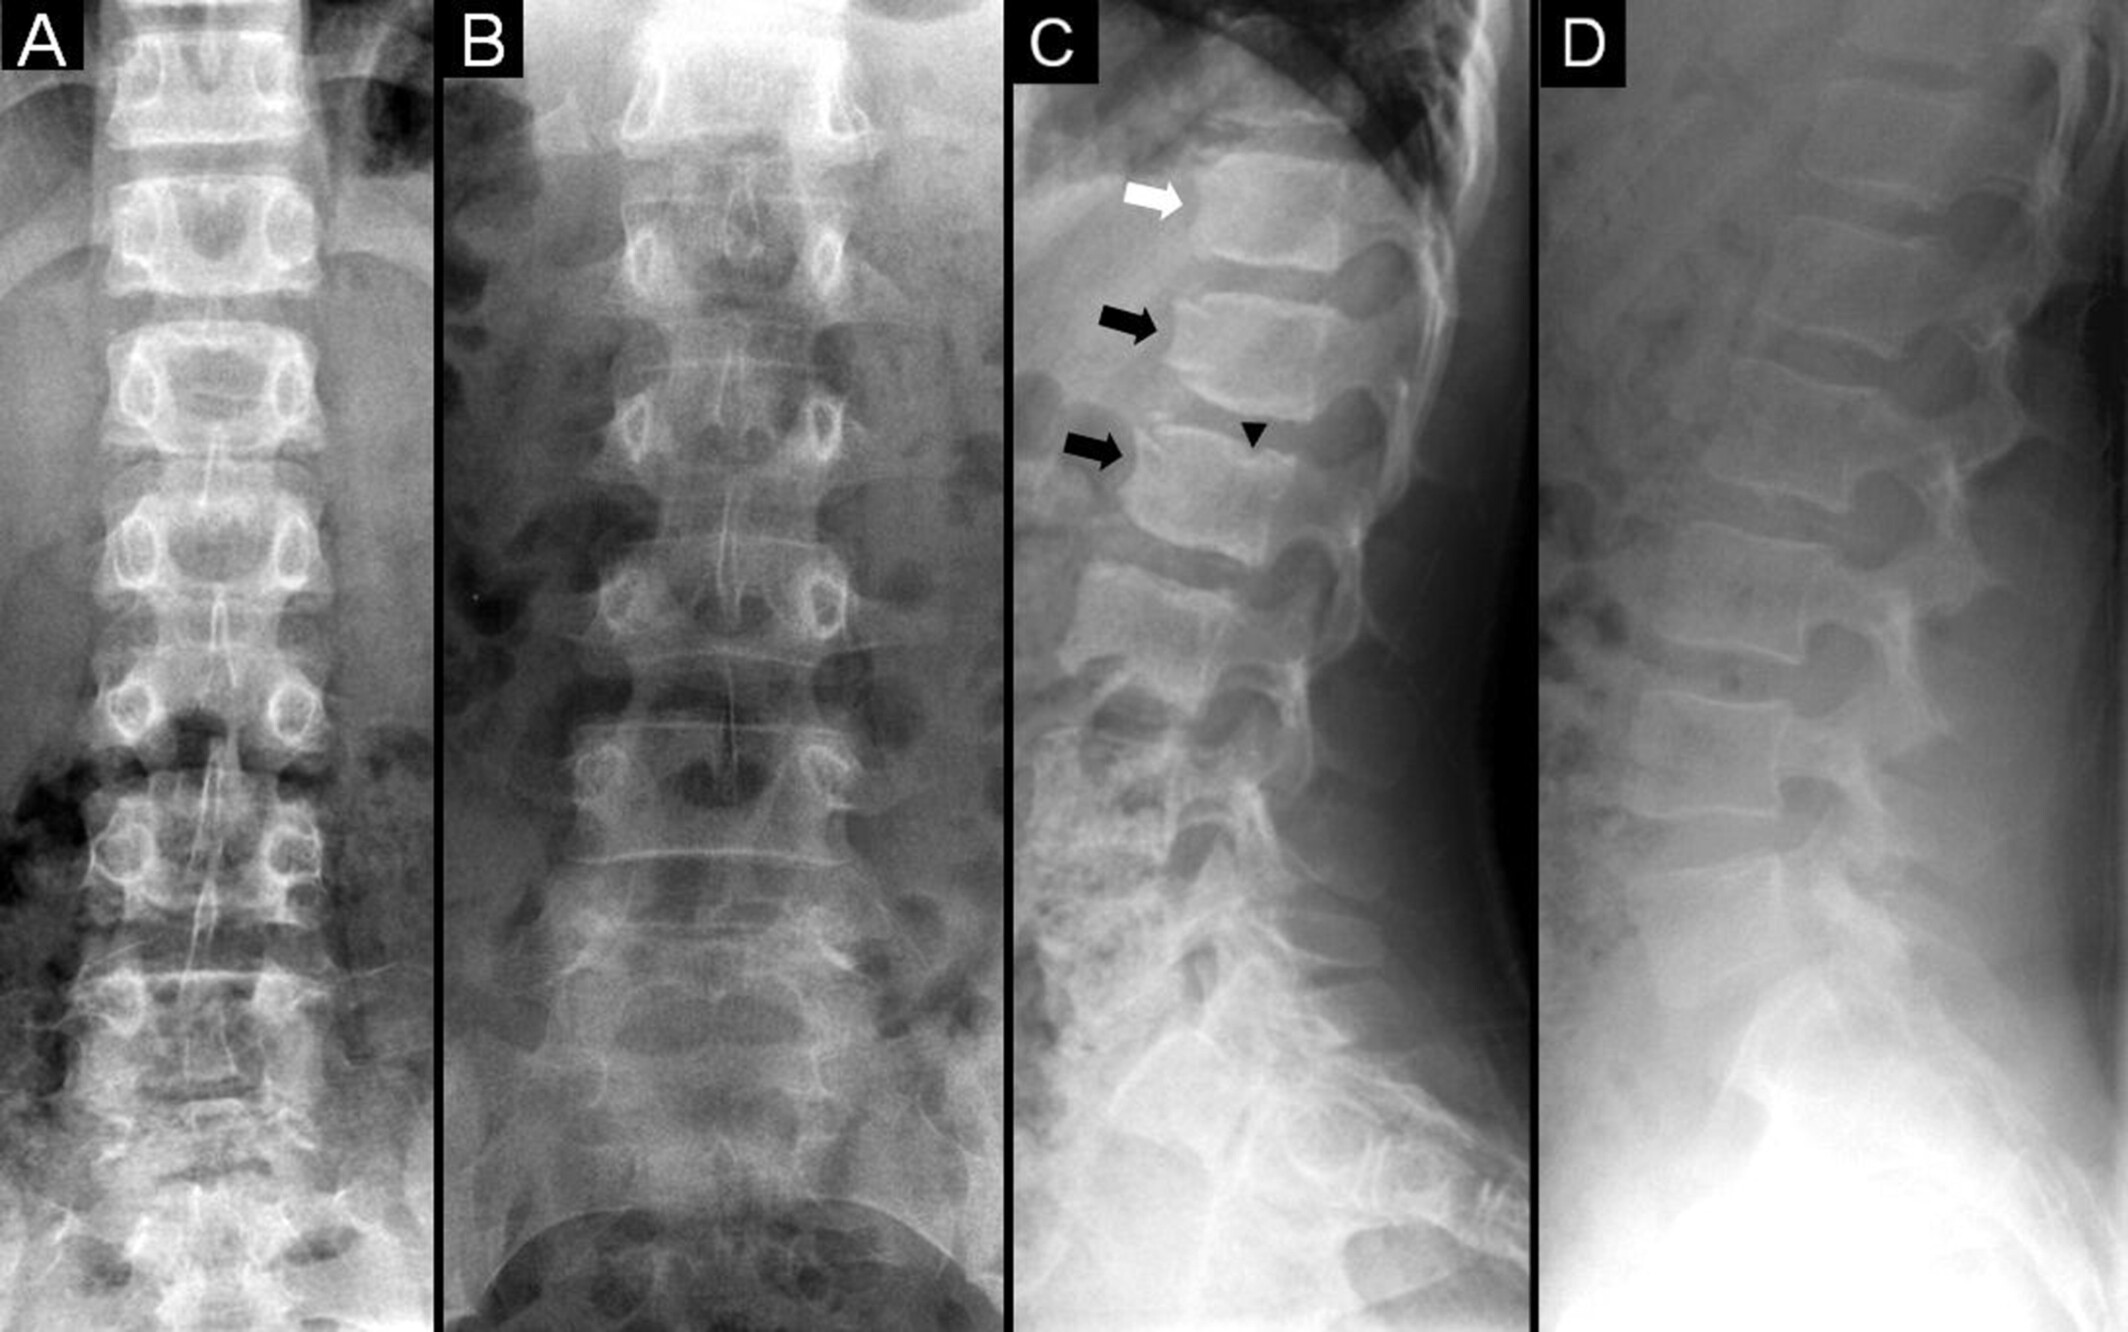

科学家们通过分析缺乏 TMCO3 基因的小鼠模型,证实 TMCO3 基因突变是导致姐妹俩身材矮小的原因。分析结果显示,小鼠的骨骼变短,从而加强了该基因与这种特殊生长异常之间的联系。